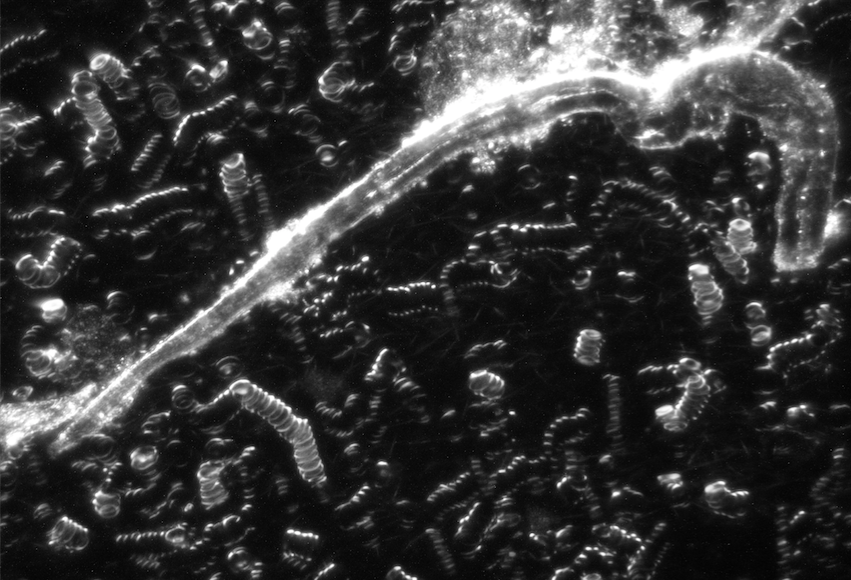

Vitalblutanalyse

Vitalblutanalyse

Vitalblut im Dunkelfeld Lichtmikroskop mit Geldrollenbildung

Vitalblut im Dunkelfeld mit diversen Auffälligkeiten

Symplast im Blut

Hier müssen mehrere Ebenen mit verschiedenen Schärfen betrachtet werden,

um eine Verunreinigung des Objektträgers auszuschließen